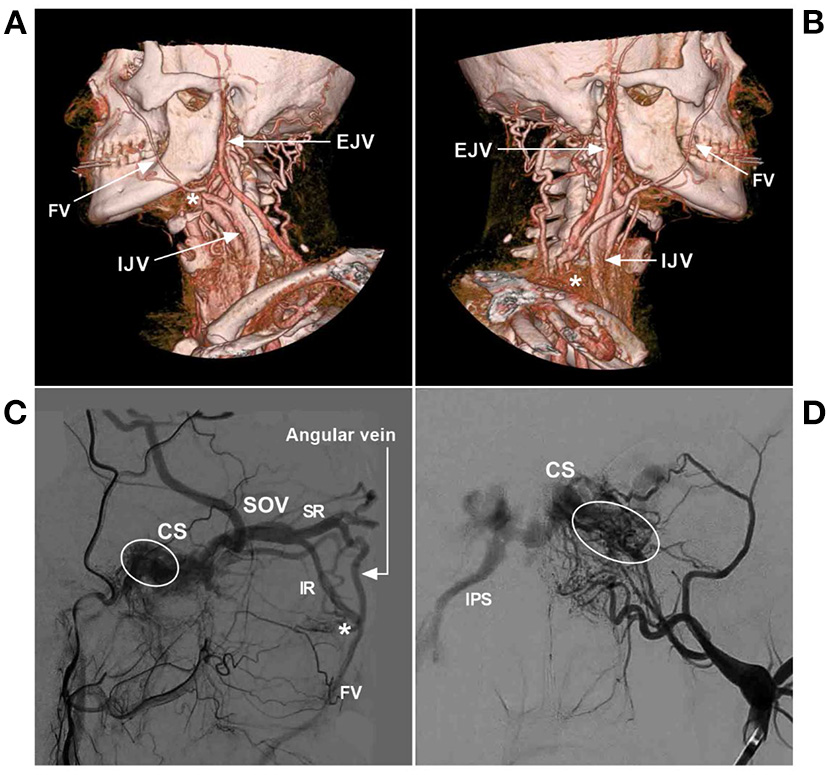

Figure 2

FV anatomy of CTA. (A) Anterior–posterior view (left) and oblique (right) view of CTA show that the SOV from the CS connected with the angular vein; then, the angular vein continued as the FV. (B) Anterior–posterior view (left) and oblique (right) view of CTA show that the typical FV descends obliquely in a straight line to continue the common FV and flow with the IJV. The asterisk (right) indicates the junction of the FV with the IJV. (C) Lateral view (left) and oblique (right) view of CTA show the FV together with the EJV into the IJV. The asterisks (left and right) indicate the junction of the FV into the IJV. (D) Lateral view (left) and oblique (right) view of CTA show that the MTV joins the STV to form the EJV and then connects with the FV into the IJV; in the face, many tidy veins join into the FV. CS, cavernous sinus; CTA, computed tomography angiography; EJV, external jugular vein; FV, facial vein; IJV, internal jugular vein; MTV, middle temporal vein; SOV, superior ophthalmic vein; STV, superficial temporal vein.